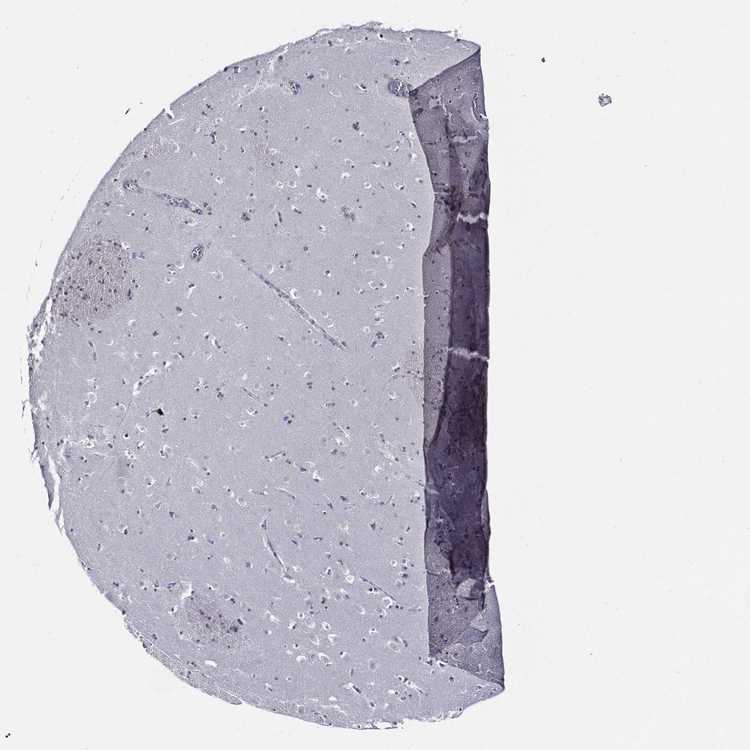

CAUDATE - Antibody stainingi

Antibody staining in the annotated cell types in the current human tissue is reported as not detected, low, medium, or high, based on conventional immunohistochemistry profiling in selected tissues. This score is based on the combination of the staining intensity and fraction of stained cells.

Each image is clickable and will lead to virtual microscopy that enables deeper exploration of all samples and also displays staining intensity scores, fraction scores and subcellular localization as well as patient and tissue information for each sample.

Antibody HPA067323

Glial cells Not detected

Neuronal cells Not detected